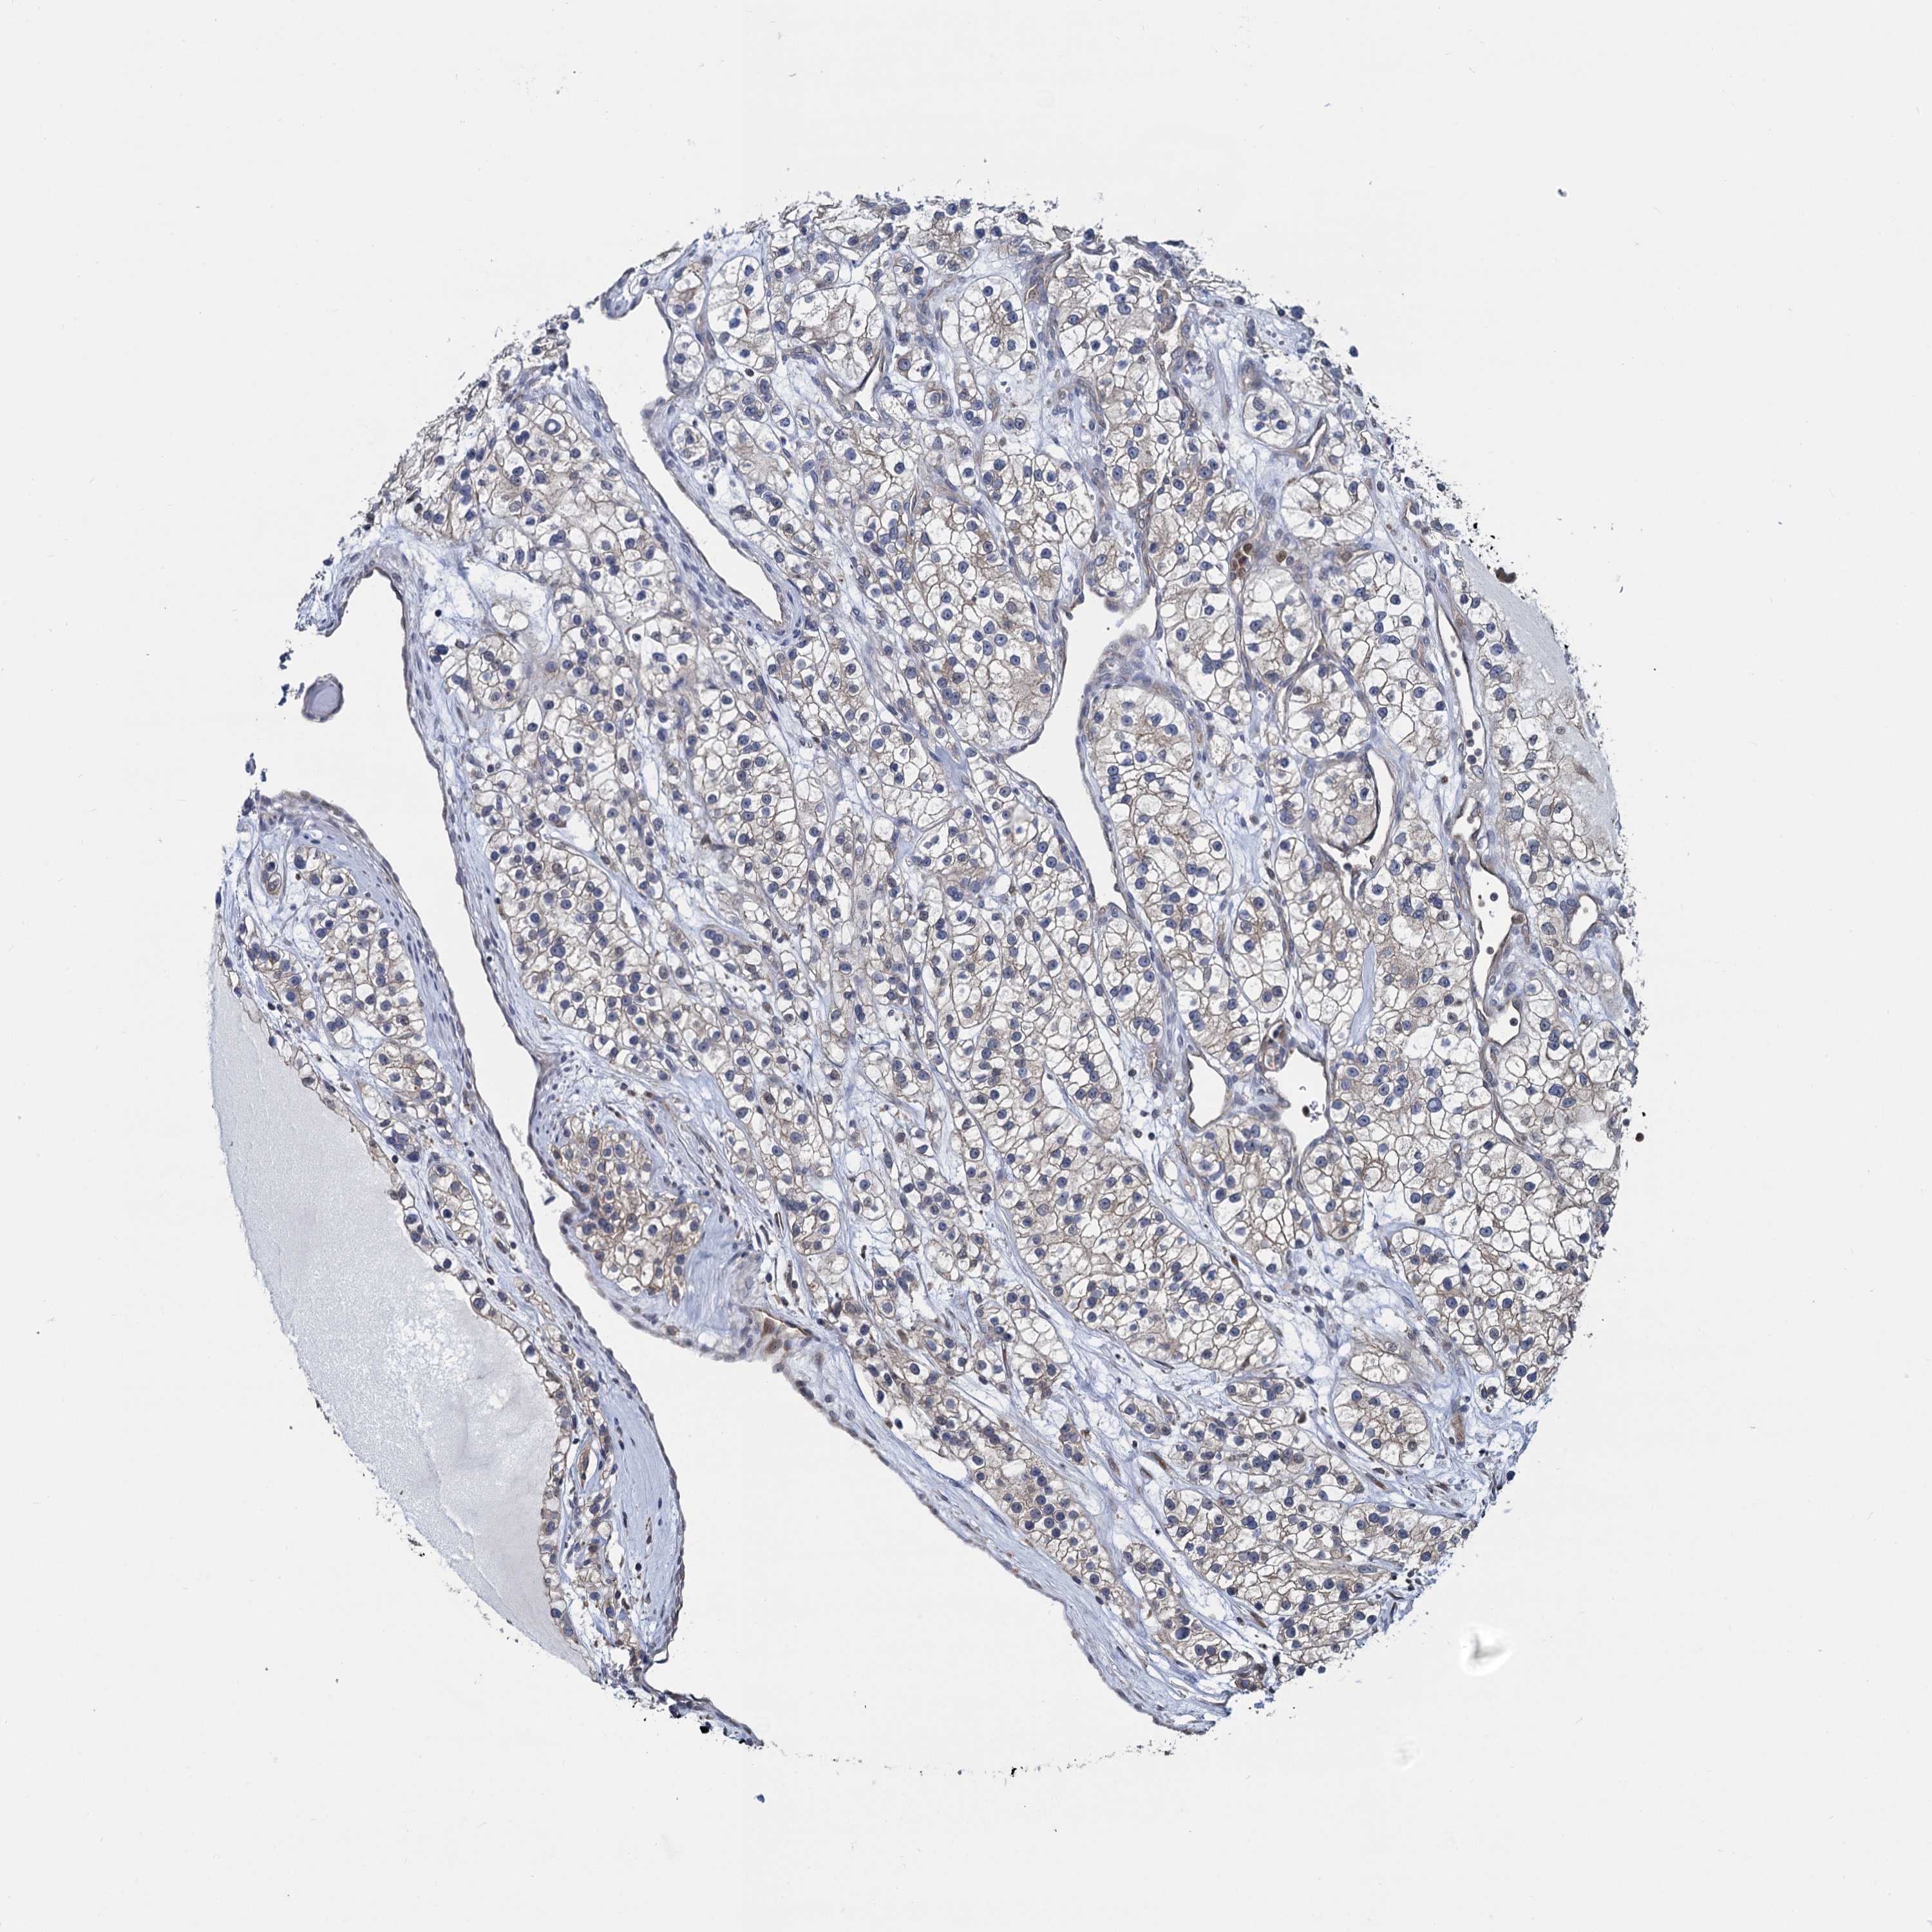

KIDNEY RENAL CLEAR CELL CARCINOMA (VALIDATION) - Interactive survival scatter ploti

The Survival Scatter plot shows the clinical status (i.e. dead or alive) for all individuals in the patient cohort, based on the same data that underlies the corresponding Kaplan-Meier plots. Patients that are alive at last time for follow-up are shown in blue and patients who have died during the study are shown in red.

The x-axis shows the expression levels (FPKM) of the investigated gene in the tumor tissue at the time of diagnosis. The y-axis shows the follow-up time after diagnosis (years). Both axes are complimented with kernel density curves demonstrating the data density over the axes. The top density plot shows the expression levels (FPKM) distribution among dead (red) and alive patients (blue). The right density plot shows the data density of the survived years of dead patients with high and low expression levels respectively, stratified using the cutoff indicated by the vertical dashed line through the Survival Scatter plot. This cutoff is automatically defined based on the FPKM cutoff that minimizes the p-score. The cutoff can be changed by dragging the vertical line or by entering a cutoff value in the square labeled "Current cut-off".

Under the Survival Scatter plot the p-score landscape (black curve; left axis) is shown together with dead median separation (red curve; right axis). Dead median separation is the difference in median mRNA expression between patients who have died with high and low expression, respectively. It is calculated as follows: median FPKM expression of dead patients with high expression - median FPKM expression of dead patients with low expression. This is intended to aid the user in visually exploring custom cutoffs and the associated p-scores and dead median separation.

Individual patient data is displayed and can be filtered by clicking on one or more of the category buttons on the top of the page. Categories describing expression level and patient information include: high, low, alive, dead, female, male and tumor stages. The scale of the x-axis can be toggled between linear and log-scale by clicking on the "x log" button. Mouse-over function shows TCGA ID, patient information and mRNA expression (FPKM) for each patient.

& Survival analysisi

Kaplan-Meier plots summarize results from analysis of correlation between mRNA expression level and patient survival. Patients were divided based on level of expression into one of the two groups "low" (under cut off) or "high" (over cut off). X-axis shows time for survival (years) and y-axis shows the probability of survival, where 1.0 corresponds to 100 percent.

RNF125 is not prognostic in Kidney Renal Clear Cell Carcinoma (validation)

Best expression cut offi

: 3.71

P scorei

N/A

Average pTPM 3.5

Number of samples 100